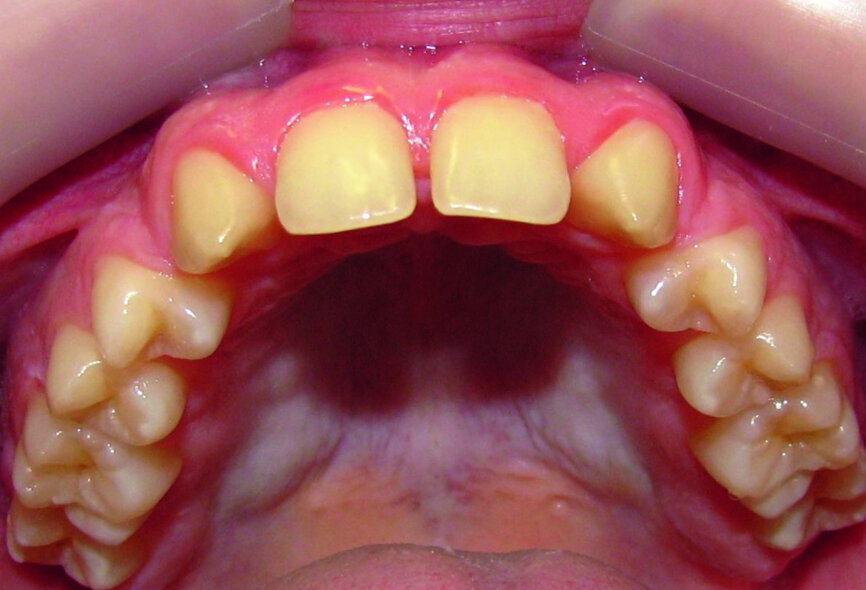

Then occlusal analysis (Figs. 11–21) was performed:

- Upper spacing due to the laterals agenesis (Fig. 18).

- Open spaces for two implants, but in the posterior area: 14 and 24.

- Substitute the laterals with canines.